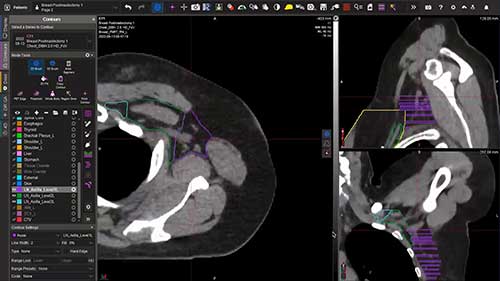

乳腺癌区域淋巴结放疗勾画01

向大家简单展示乳腺癌区域淋巴结照射之前,心脏等危及器官的勾画过程。